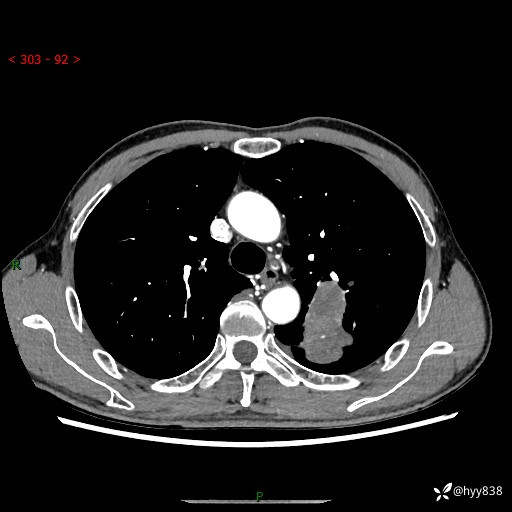

现病史:患者余4月前发现咳嗽咳痰伴痰中带血,无胸闷、胸痛、头晕、恶心、呕吐等不适,2天前因体检发现肺部结节遂于当地市第一人民医院行胸部CT薄层平扫+三维重建示:1.左肺上叶尖后段占位性病变考虑肿瘤性病变伴阻塞性肺炎,右肺上叶后段磨玻璃结节。2.肝内多发囊性灶、左肾结石。现患者为求进一步治疗,于我院门诊就诊,门诊以“肺结节”收入院。 自患病以来,精神、饮食、睡眠尚可,大小便正常,体力体重无明显减轻。

胸部CT增强扫描(外院平扫)